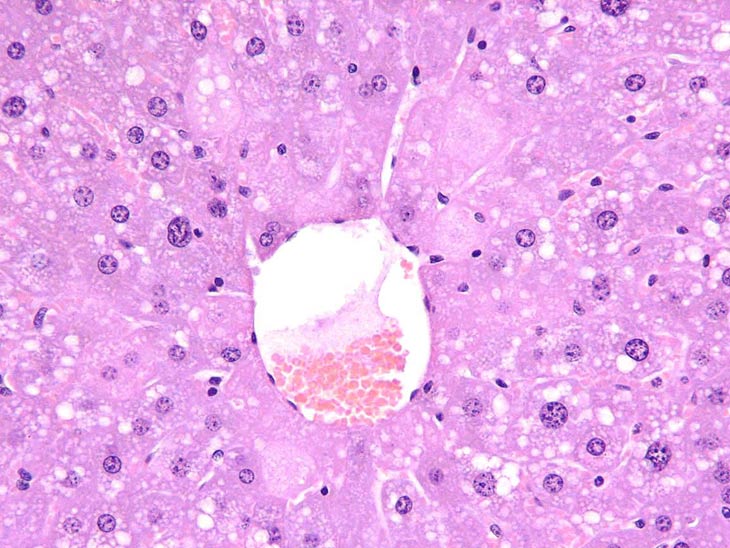

Mild centrilobular necrosis is evident following treatment with acetaminophen.

Another example of mild centrilobular necrosis induced by acetaminophen treatment. Note nuclear and cytoplasmic changes in hepatocytes surrounding the central vein.